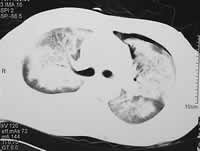

入院时床旁X线胸片可见右肺和左上肺大片状致密影,两侧肋膈角钝。1月24日X线胸片肺内阴影已有吸收,但尚有较多的斑片影。2月2日双肺实变影已明显吸收,同时看到双上肺增粗的肺纹理,还有一些纤维索条影。1月18日胸部高分辨率CT见双肺大片实变影,有支气管充气征,似地图样改变(图1)。2月10日复查CT纵膈窗胸腔积液已消失,肺窗可以看到纤维条索影和磨玻璃影。

图1

胸部CT